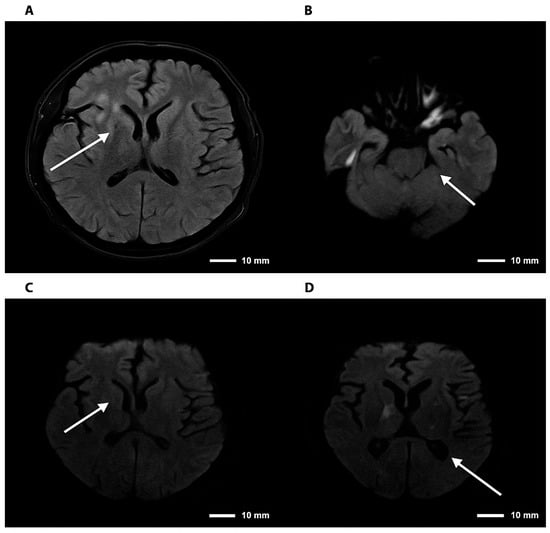

Central nervous system (CNS) cryptococcosis caused by Cryptococcus neoformans is a severe opportunistic infection that primarily affects individuals with impaired cellular immunity. Although the classic presentation includes headache, fever, and meningeal signs, chronically immunosuppressed patients may develop atypical neuropsychiatric manifestations, leading to diagnostic delays. We report the case of a 53-year-old man with rheumatoid arthritis (RA) receiving long-term prednisolone and etanercept therapy, who presented with a 7-day history of depressive mood, anhedonia, social withdrawal, irritability, and progressive confusion. Neurological examination revealed disorientation without focal deficits. Brain imaging showed only mild cortical atrophy, and cerebrospinal fluid (CSF) analysis revealed lymphocytic pleocytosis, low glucose, and elevated protein levels. Multiplex PCR (FilmArray®) of CSF identified Cryptococcus neoformans, CSF positive to C. neoformans. The patient was treated with liposomal amphotericin B followed by fluconazole, resulting in gradual improvement of both neurological and psychiatric symptoms. This case highlights an unusual presentation of CNS cryptococcosis in a non-HIV immunosuppressed patient with RA, emphasizing that acute psychiatric or cognitive changes can be the predominant manifestation. Clinicians should consider fungal infections in the differential diagnosis of acute neuropsychiatric symptoms in patients receiving chronic corticosteroid and biologic therapy. Early recognition and molecular diagnosis can facilitate timely antifungal treatment, potentially improving prognosis and reducing morbidity associated with delayed therapy. This report underscores the importance of awareness of atypical presentations of opportunistic infections in immunosuppressed populations. Full article

Figure 1